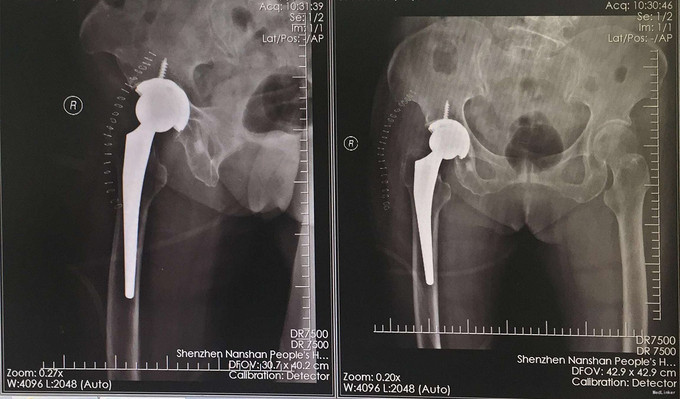

诊断:右股骨颈骨折 治疗:全髋关节置换术

术后第二天开始下地,术后5天出院。术后一个月随访,活动满意。